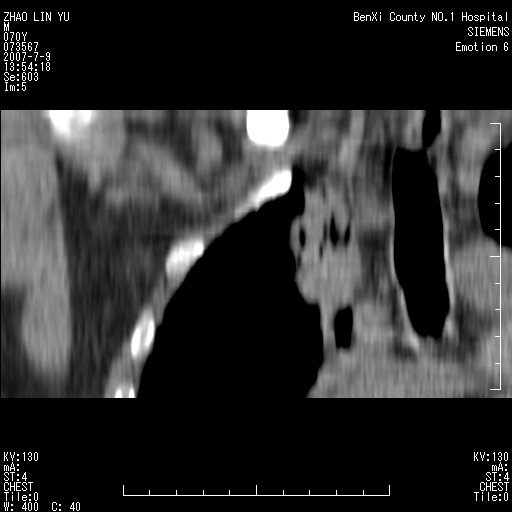

以下是引用王靖旗在2007-7-10 17:12:00的发言:[br] 男、70、咳嗽两个月,半年前换瓣手术,胸片未见异常,于昨天行x片发现右肺上野大片影,行ct扫描,这里是减薄图像,余肺正常。明天晚上会有增强扫描片,到时我会上传。[br][br] 冠状位请大家细看,应该是有意义的,[br][br] 请大家先看平扫发表意见。[br][br]

[br]冠状面[br]